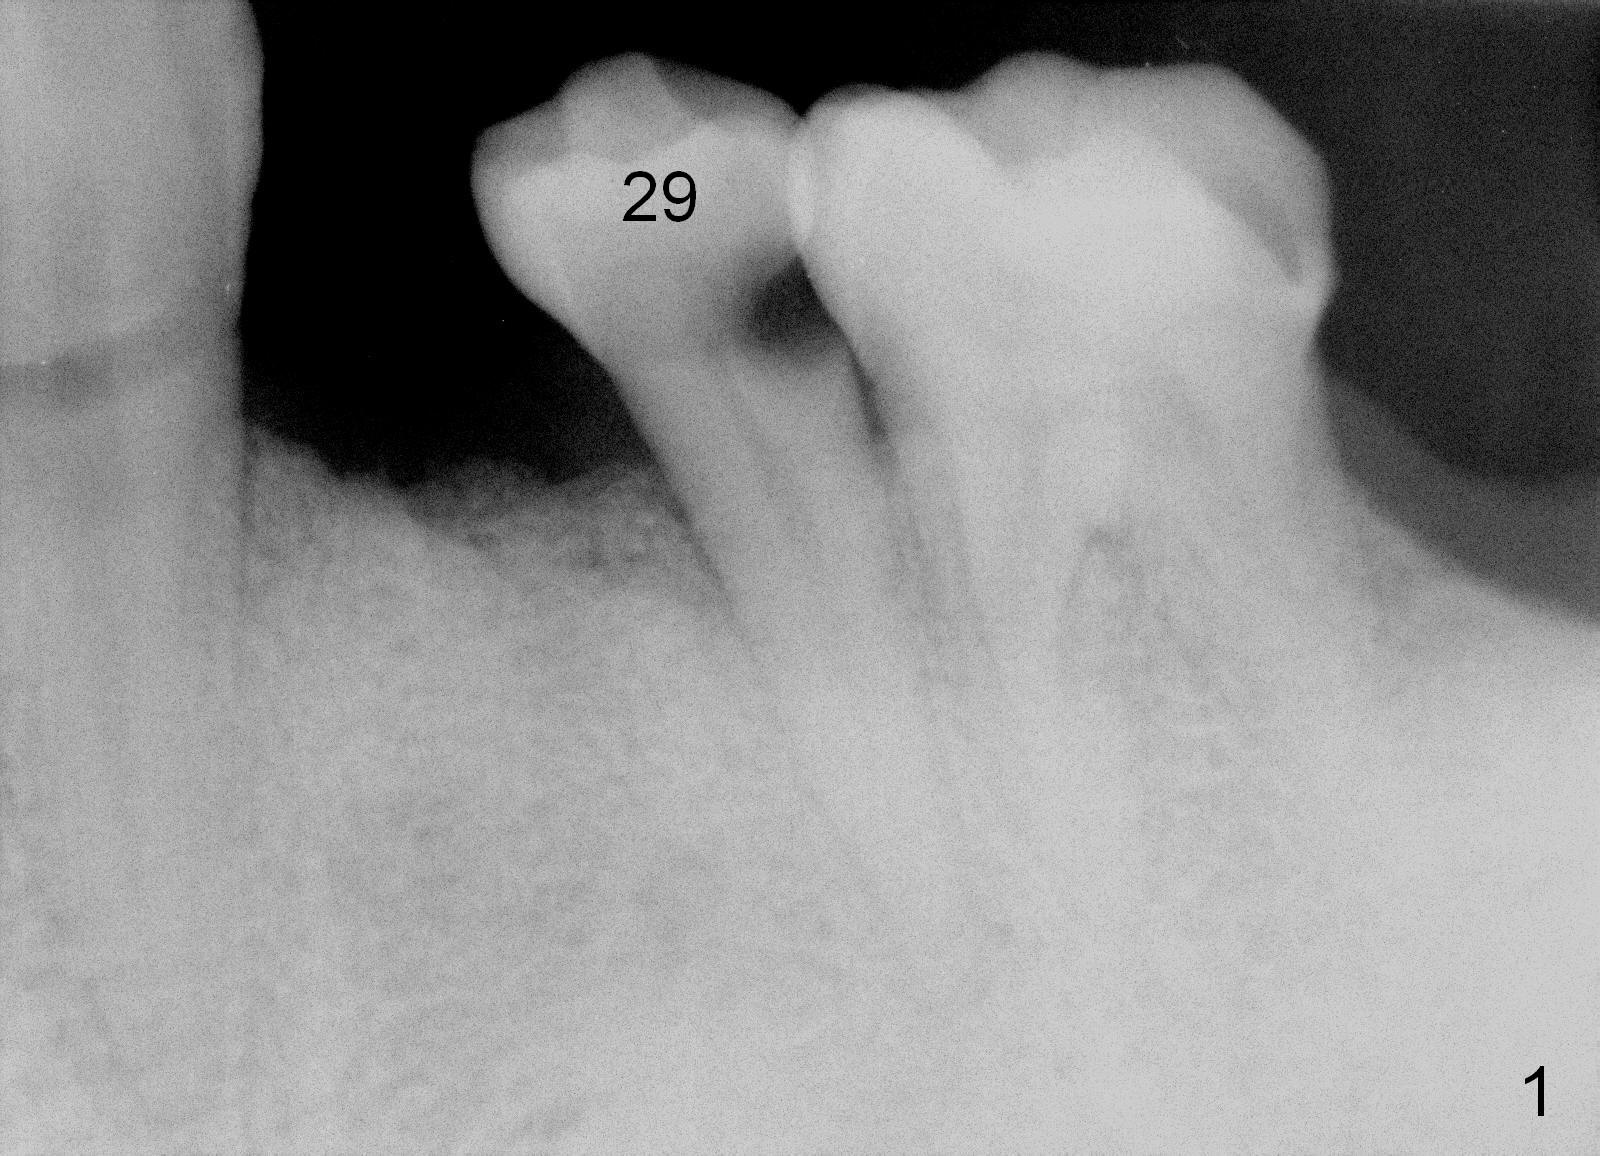

A 56-year-old man has poor dentition (Fig.1).  The tooth #20 fractures (not shown) after root canal therapy (Fig.2).  A 4.5x14 mm bone-level implant is planned (Fig.3).